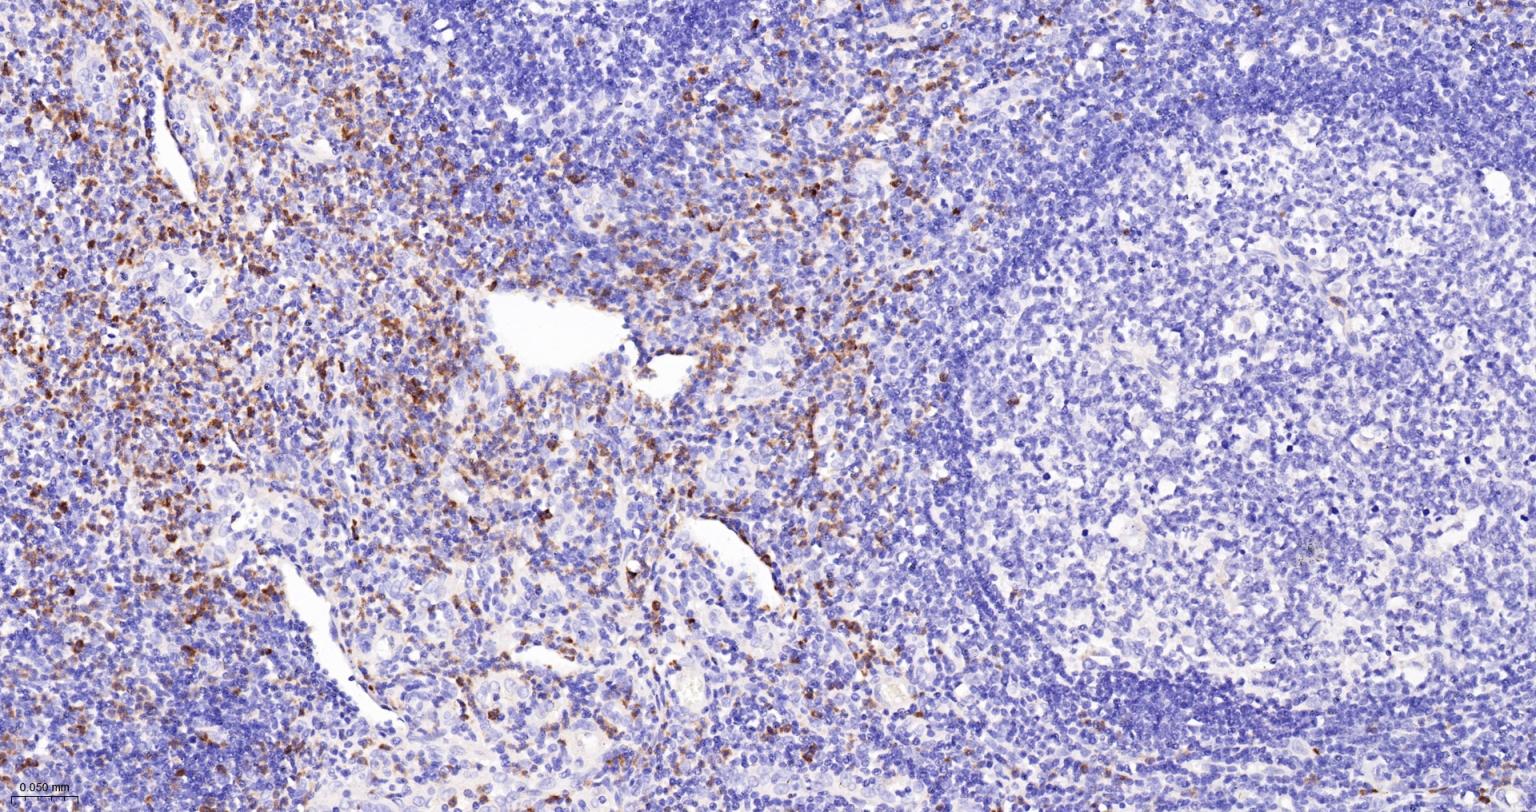

Paraformaldehyde-fixed, paraffin embedded Human Spleen; Antigen retrieval by boiling in sodium citrate buffer (pH6.0) for 15 min; The section was incubated with MMP8 Monoclonal Antibody, Unconjugated (bsm-63138R) at 1:200 overnight at 4°C, followed by conjugation to the bs-0295G-HRP and DAB (C-0010) staining.

Paraformaldehyde-fixed, paraffin embedded Human Pyogenic appendicitis; Antigen retrieval by boiling in sodium citrate buffer (pH6.0) for 15 min; The section was incubated with MMP8 Monoclonal Antibody, Unconjugated (bsm-63138R) at 1:200 overnight at 4°C, followed by conjugation to the bs-0295G-HRP and DAB (C-0010) staining.